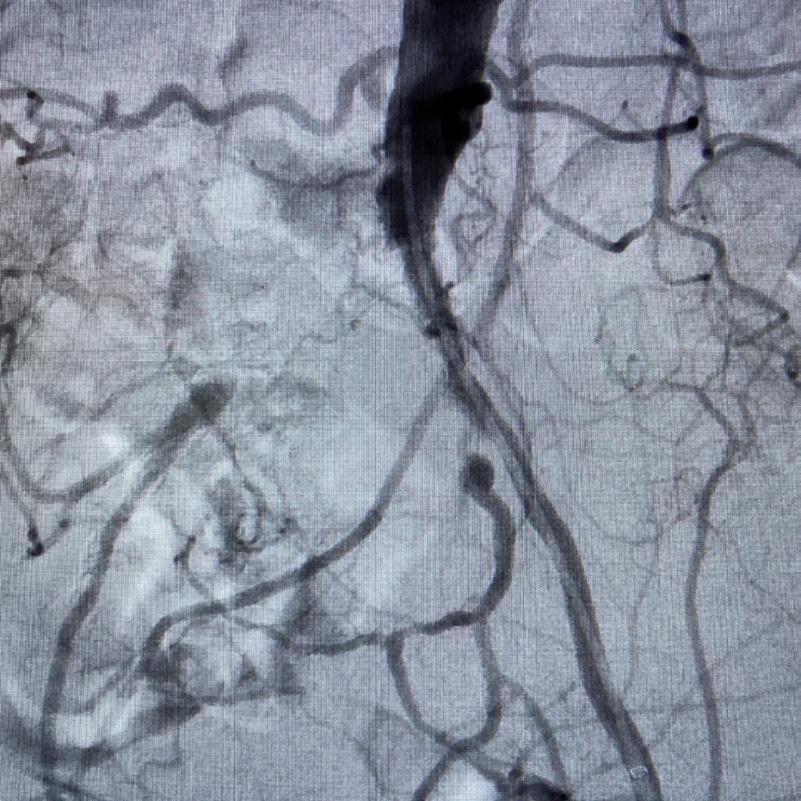

Case 2: The Shockwave M5+ tackles 90% stenosis of the distal SFA

The patient is a 75-year-old man with a history of hypertension, hyperlipidemia, CAD, chronic kidney disease and diabetes mellitus, who presents with a non-healing wound of the right lower extremity for three months.

He had undergone diagnostic work—his ankle-brachial index (ABI) was found to be 0.73 with a toe pressure of 50mmhg, and a duplex ultrasound revealed a densely calcified superficial femoral artery (SFA) stenosis of 90%.

He was taken to the cath lab and underwent a right lower-extremity arteriogram. This confirmed a 90% stenosis of the distal SFA, with normal three-vessel run off.

Due to the heavy calcium, we opted for a Shockwave M5+ 6x60mm and delivered 200 pulses to the lesion. There was no appreciable residual stenosis at the completion of the procedure, and his post-procedure ABI improved to 1.

Figure 1. Pre-procdural CTA Figure 4. Graft delivery Figure 1. Pre-procedural angiogram Figure 2. Pre-procedural angiogram Figure 5. Final angiogram Figure 2. IVL treatment angiogram Figure 3. Post-IVL angiogram Figure 6. Post-procedural CTA Figure 3. Final angiogram